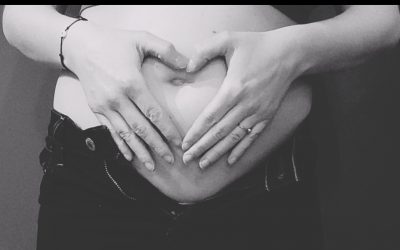

La scoliose, qu’est-ce-que c’est ?

La scoliose est une déviation sinueuse de la colonne vertébrale dans les trois plans de l’espace: inclinaison dans le plan frontal, rotation des vertèbres dans le plan horizontal et inversion des courbures dans le plan sagittal. Il s’agit d’une...